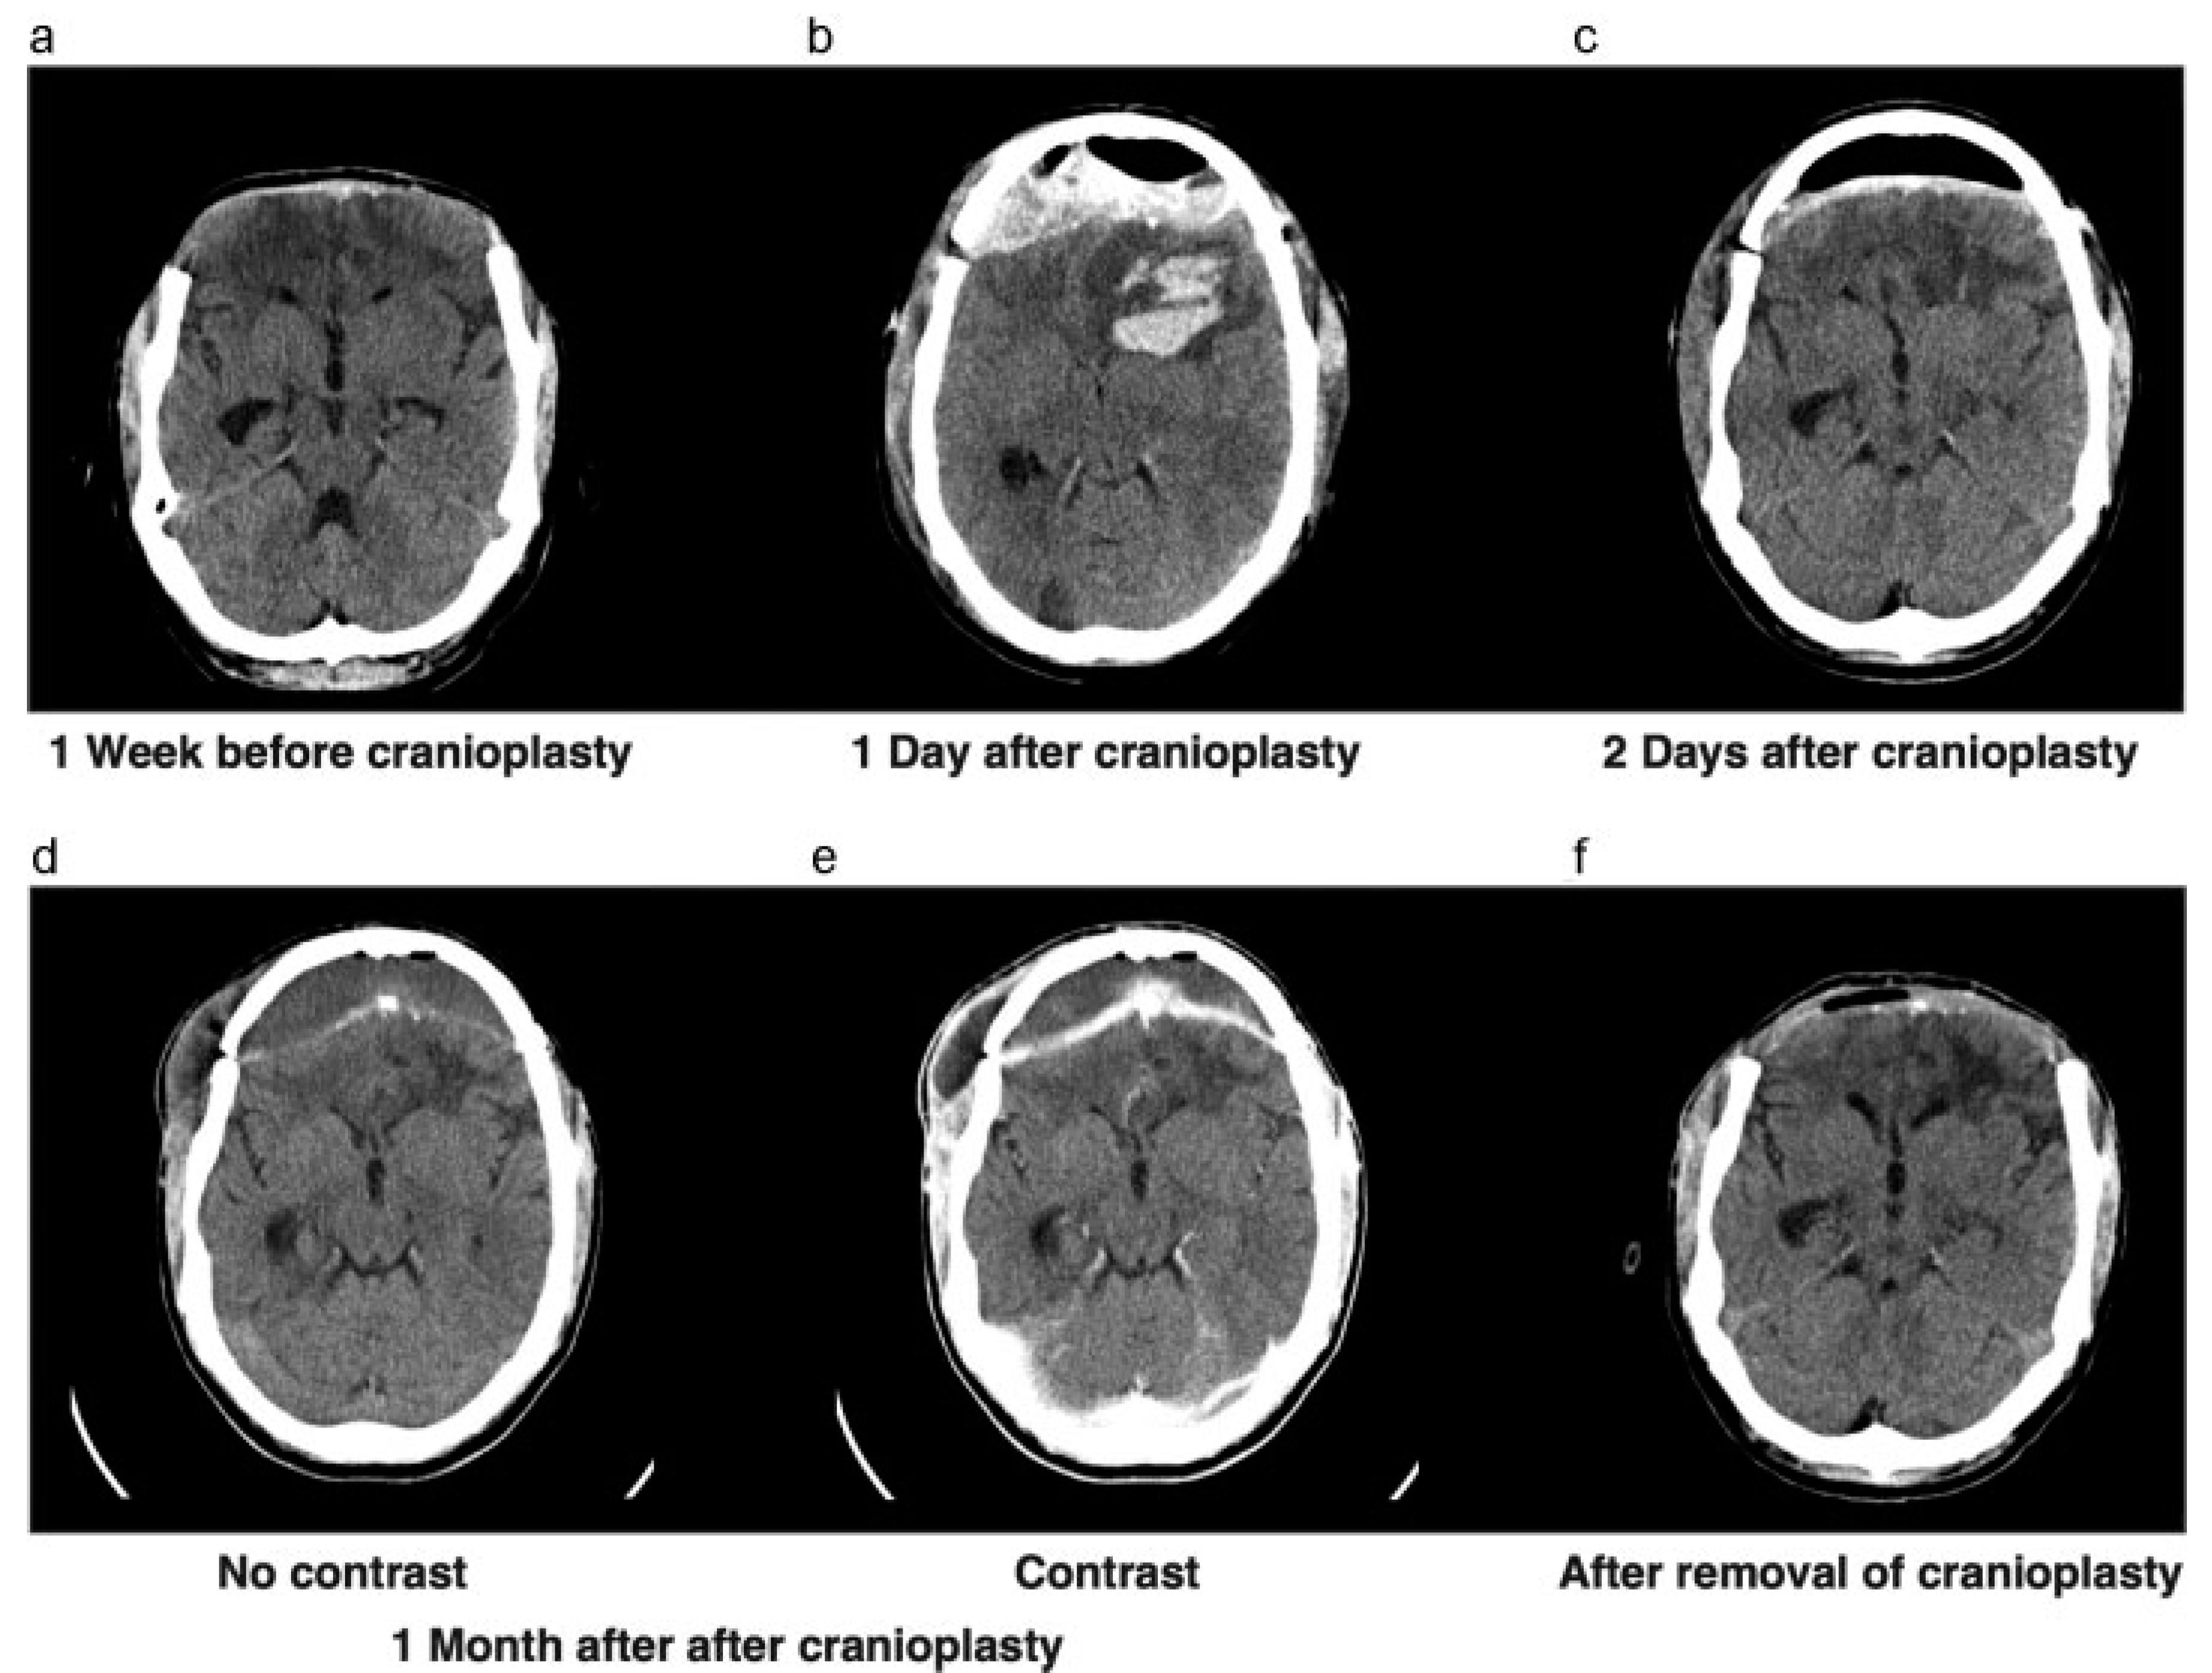

Approximately 2 months later, the cerebral swelling had diminished to the extent that we decided to perform a cranioplasty with the autograft (Figure 2a). After the cranial reconstruction, the anticoagulant, which was temporarily stopped before surgery, was readministered. Unfortunately, after surgery the patient showed neurologic deterioration based on an epidural hematoma that had to be evacuated immediately and the bone graft was left in place (Figure 2b,c). After surgery, the patient showed good recovery and went to a cognitive rehabilitation center. However, because of his altered cognitive behavior, we had concerns regarding bone graft infection and wound closure.

One month later, the patient returned with swelling around his right eye, close to the scar. A CT scan showing subcutaneous and epidural collections, in addition to elevated infection parameters in laboratory findings, suggested an infected bone flap (Figure 2d,e). The bone flap was removed and discarded (Figure 2f) and intravenous antibiotics were administered. A 3D CT scan was performed to evaluate the bone defect for a future allograft (Figure 3c–e). In the meantime, a custom-made helmet was worn to protect the brain.

Figure 2. (a) CT scan showing leveling of the brain with bone edges, prior to returning the autograft. (b) CT scan showing epidural and intraparenchymal hematoma 1 day after cranioplasty. (c) CT scan after evacuation of epidural hematoma. (d,e) CT scan before and after contrast showing swelling of right-sided subcutaneous tissue, with contrast enhancement of the dura. (f) CT scan after removal of infected bone graft.